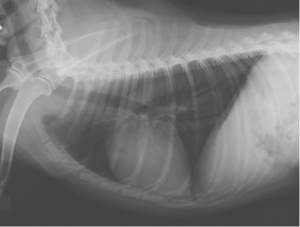

コメント;

CTより肋骨から派生した腫瘍が疑われました。CTでも明らかな肺転移は確認されませんでした。